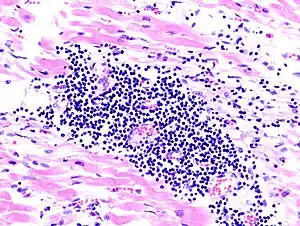

Miocardite de células gigantes:

Isto é raro, e obtém seu nome de células anormais que desenvolvem no coração. A causa não é conhecida mas tende a desenvolver em algumas pessoas que têm um timona (um crescimento da glândula de timo), lupus eritomatoso sistêmico ou tirotoxicose.